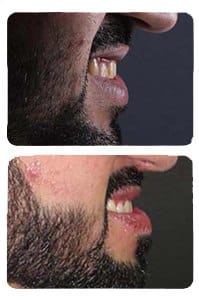

حالة 37: علاج عضة عميقة وتهيئة للزراعة

ابتسامات, بروز أسنان أمامية علوية, عضة عميقة, فراغات بين الأسنان, نقص في سن أو عدة أسنان

ابتسامة-36

أسنان منطمرة في العظم, أضراس خلفية مائلة, ابتسامات, ازدحام أسنان, بروز أسنان أمامية علوية, بروز مضاعف للأسنان الأمامية, عضة عميقة, عضة معكوسة أمامية, عضة معكوسة خلفية, عضة مفتوحة, فراغات بين الأسنان, نقص في سن أو عدة أسنان